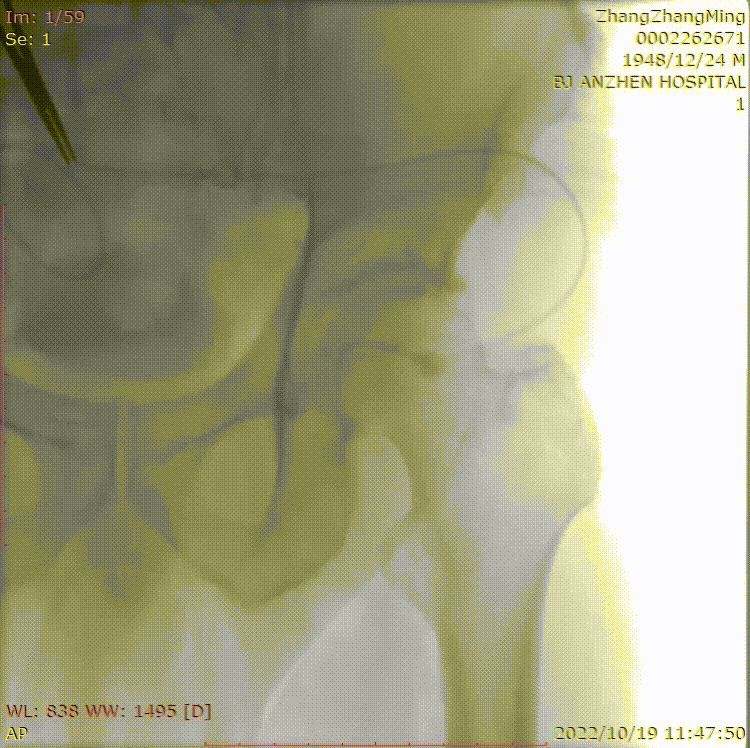

中等长度 、轻微钙化的股浅动脉病变

股浅动脉中等长度病变(10-20cm)合并轻微钙化,因病变范围适中、钙化程度较轻,需兼顾 “微创开通” 与 “长期通畅”。巧克力球囊凭借均匀扩张、低血管损伤的核心优势,成为这类病变的理想选择,可高效完成血管准备,适配 “无支架” 治疗理念。

★ 巧克力球囊

Chocolate 5-120mm

除近端残余狭窄外,效果良好